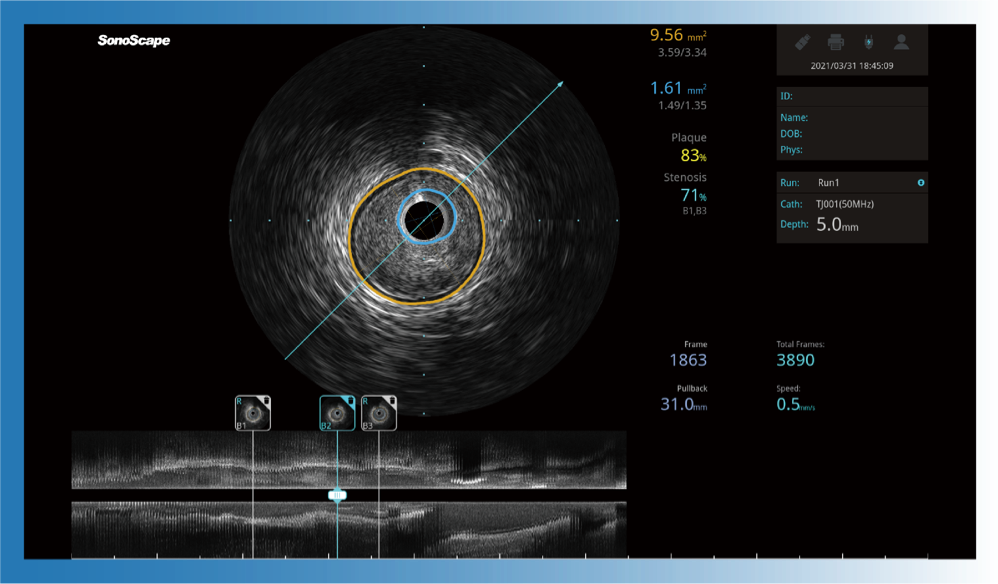

• 米兰官方网站宽频IVUS图像

对比传统IVUS导管成像,米兰官方网站宽频IVUS图像的近场支架梁显影更细腻,远场中膜外血管仍清晰可辨,兼顾远中近,兼顾分辨力与穿透深度

一键智能描迹,自动测量斑块负荷、面积狭窄率等指标,准确率高于90%